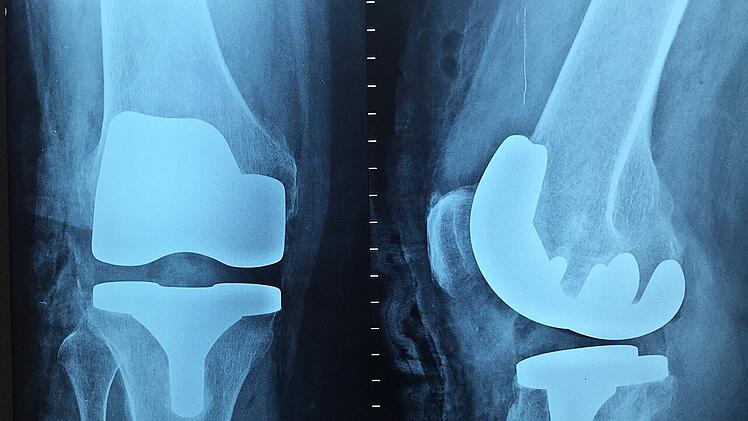

Ein künstliches Kniegelenk im Röntgenbild.